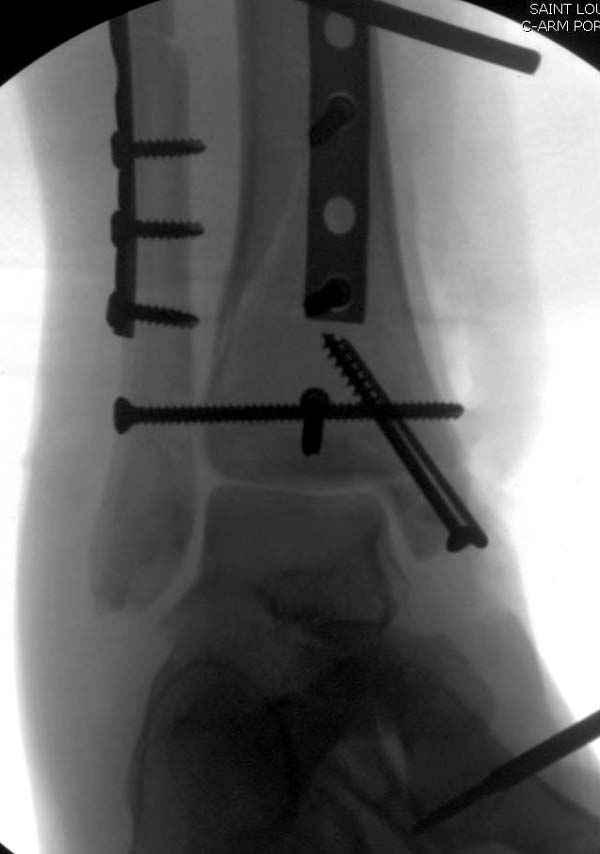

Из заднего доступа остеотомия тонким остеотомом и коррекции на ЭОПе.

Без применения сложной конструкции, а обычными параллельными шурупами. Шурупы в 3.5 мм и дополнительно фиксация крючковидной пластиной, сделанной из 3.5 mm semitubular пластиной, Butress или аntiglade фиксация.

Здесь алгоритм фиксации свежего перелома и преоперационный план для обсуждаемого случая.

Djoldas Kuldjanov, MD

Department of Orthopedic Surgery

St. Louis University Medical Center